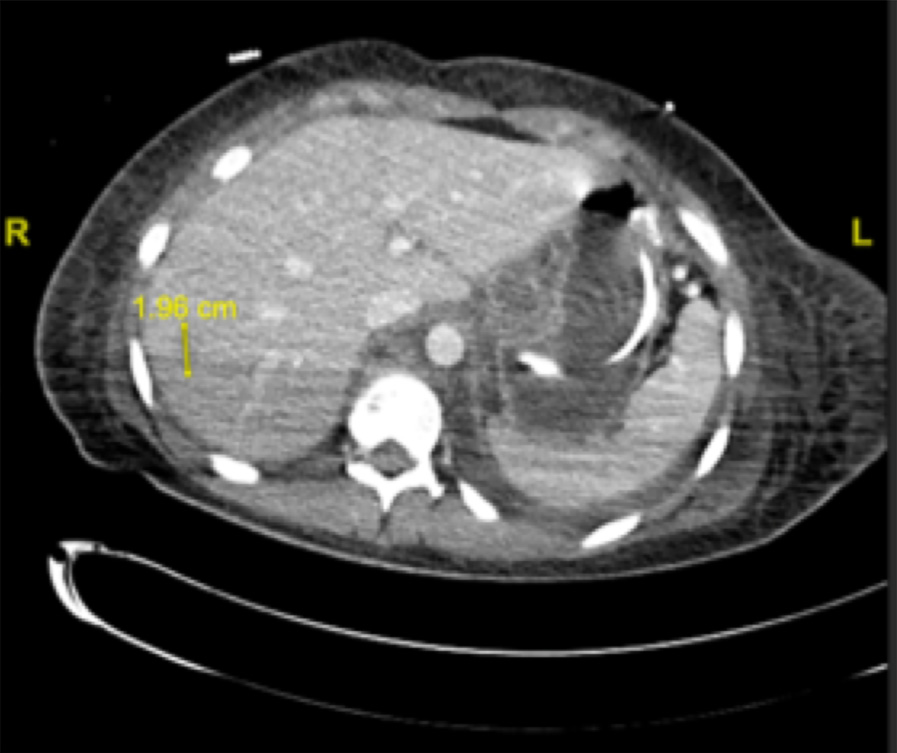

和上腔静脉综合征。MRI和CT扫描的进一步分期显示转移至其右侧脑尾状核和右肝后外侧叶(图7、8)。患者开始接受放射治疗,但在接受了两次纵隔肺部肿块的放疗后,决定停止放疗,因化疗后症状迅速改善,仅继续化疗。7月开始使用阿来替尼3个月后,该患者几乎无症状,氟脱氧葡萄糖

PET扫描显示改善,包括肺实变明显减少但仍持续存在的胸腹部淋巴结病变,淋巴结转移和双侧胸腔积液消退。

图8 CT扫描显示右肝20 mm模糊低增强病灶,可疑肝转移。